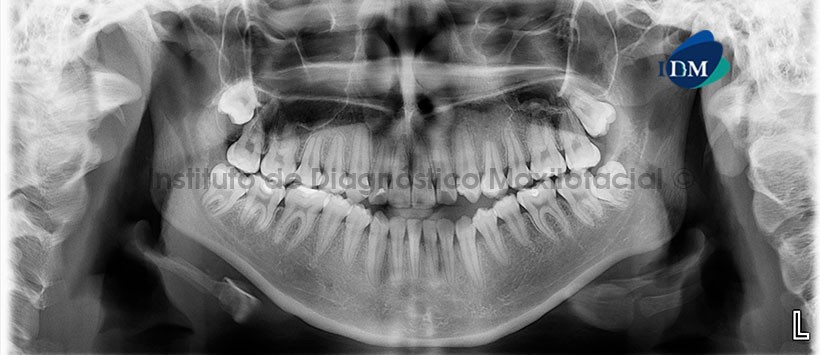

En la radiografía panorámica (Figura 1) se observa neumatización alveolar y anterior de los senos maxilares, a predominio del lado derecho. Se visualiza, además, una imagen radiolúcida de límites definidos y bordes corticalizados proyectados sobre la apófisis cigomática del hueso temporal del lado izquierdo.